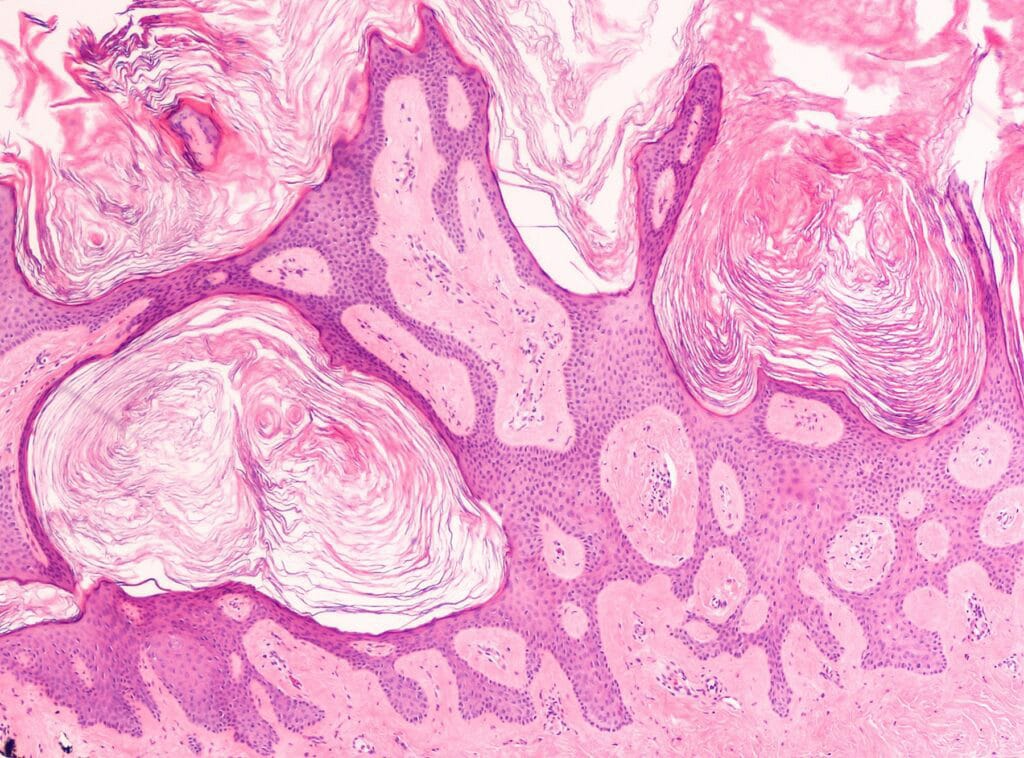

Seborrheic keratoses are common, non-cancerous growths of the outer layer of the skin which first appear during adult life. As time goes by, more growths will appear and existing growths will enlarge and become thicker.

They begin as slightly raised, light brown or yellow spots. Gradually they thicken and take on a rough, warty, and sometimes waxy surface. They soon may darken and may turn gray or black.

Seborrheic keratoses are superficial and look as though they were stuck on the skin. Persons who have had several keratoses can usually recognize this type of benign growth. However, if you are concerned or unsure about any growth, please call for an appointment so that we can examine and/or biopsy changing or growing lesions.